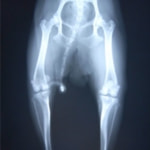

■ 症例24 キャバリア 7か月

左右膝蓋骨内方脱臼(左:グレードⅣ 右:グレードⅢ)

以前から左右後肢の跛行が認められ、整形外科学的検査・レントゲン検査により左右の膝蓋骨脱臼が認められた。症状が重度である左膝の膝蓋骨脱臼整復術を行った。外科手技は縫工筋及び内側広筋の解放、脛骨粗面の外側転位、滑車ブロック形造溝術、内外側関節方の縫縮を実施した。術後一か月時点で、左の膝蓋骨は安定しており経過は良好である。

本症例は成長期における重度の膝蓋骨脱臼であり、術後の再発の可能性もあるため、経過をしっかりと観察していく必要がある。また、今回手術を実施していない右膝に関しても経過を観察し、手術を検討していくこととする。